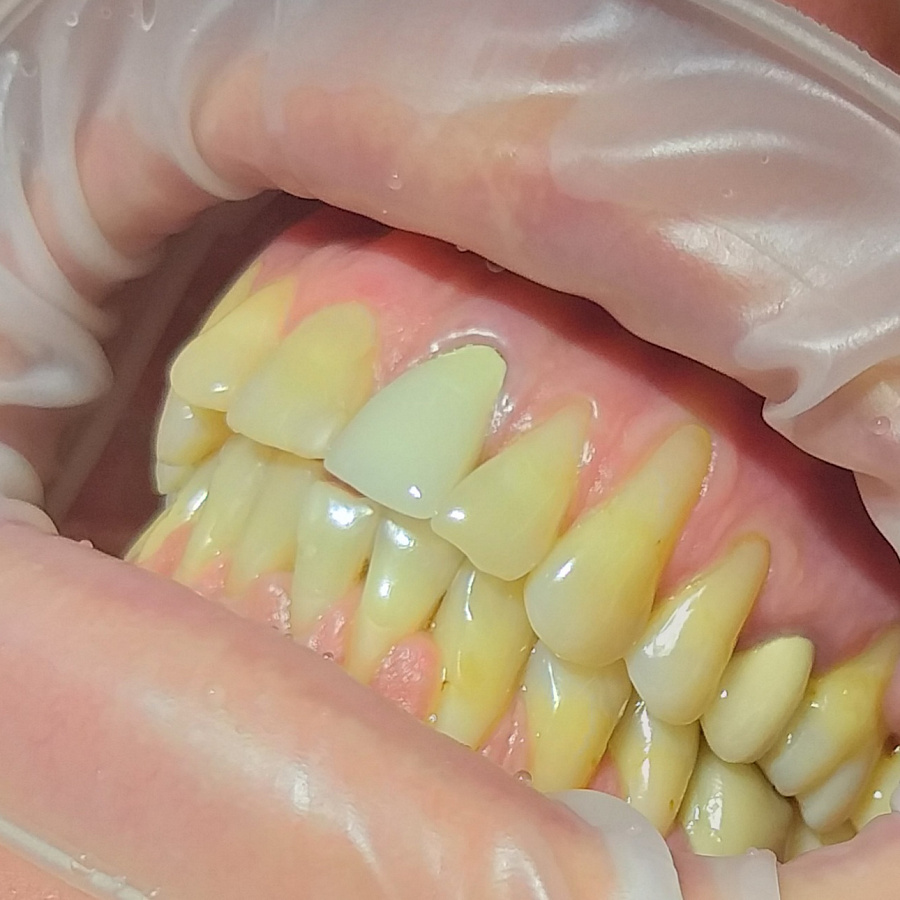

Пациент обратился в клинику с жалобами на оголение шеек и корней зубов, повышенную чувствительность зубов от холодного, горячего и других пищевых раздражителей, боли во время чистки зубов, косметический дефект.

Поставлен диагноз генерализованная рецессия десны в области зубов верхней и нижней челюстей, аномалии положения зубов